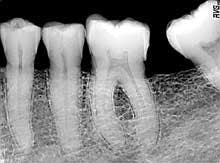

Because the image is binary code and not analog, software algorithms can enhance dentists' diagnostic abilities, enabling them to easily "extract" certain features from the digital image with the click of a mouse. Many digital images have a very wide dynamic range, containing as many as 4,098 shades of gray (or 12-bit). Even though Windows only can display 256 shades and the human eye is limited to even less (16 to 20 gray shades), these software tools present the 16 to 20 shades that are best-suited to what you are looking for, whether it be caries, lamina dura, trabecular bone, DEJ, calculus, radiolucencies, etc.

1 Image quality — Purchase the highest-resolution system that you can so the finest clinical details will be visible. The image is everything!